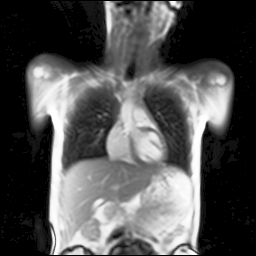

Refer to captionRefer to captionRefer to captionRefer to captionRefer to captionRefer to captionRefer to captionRefer to captionRefer to captionRefer to captionRefer to captionRefer to captionRefer to captionRefer to caption

Figure 5: Maximum inspiration (top row) and maximum expiration (bottom row) for different slice positions of one patient from back to front.

For a complete chest volume coverage, the lung is scanned at different slice positions as shown in Figure 5. At each slice position, a dynamic 2D+t image series with 140 images is acquired. For the further analysis of the image data, all images of one slice position need to be spatially aligned. We choose the image which is closest to the mean respiratory cycle as fixed image of the series. The other images of the series are then registered to this image. Our data set consists of 48 lung acquisitions of 42 different patients. Each lung scan contains between 7 and 14 slices. We used the data of 34 patients for the training set, 4 for the evaluation set, and 4 for the test set.